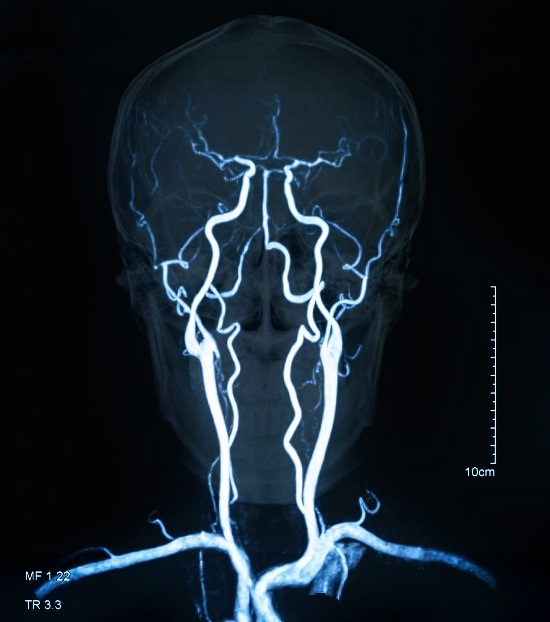

- Магнитно-резонансная ангиограмма — это неинвазивное исследование, которое оценивает состояние артерий головы и шеи. Сканирование направлено на выявление аневризм, стеноза и атеросклеротических бляшек.